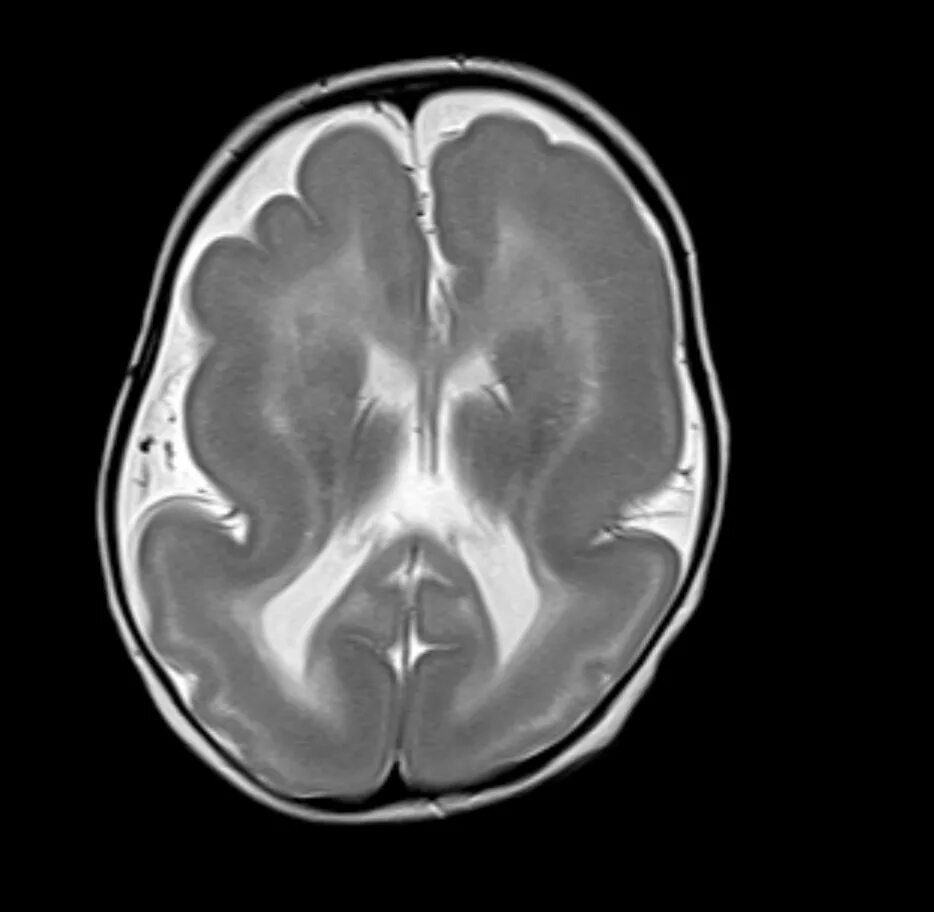

Пример лиссэнцефалии на МРТ: широкие и плоские извилины с мелкими единичными бороздами в лобных долях, а также в теменно-затылочных областях. Боковые желудочки расширены, белое вещество слабо развито.

Сильвиевы щели расположены вертикально, мозг при этом имеет вид неправильной восьмерки, как на примере ниже:

МРТ, режим Т2-ВИ: неполная лиссэнцефалия в сочетании с фокальной пахигирией (широкие и плоские извилины) в правой лобной доле, деформация задних рогов боковых желудочков мозга